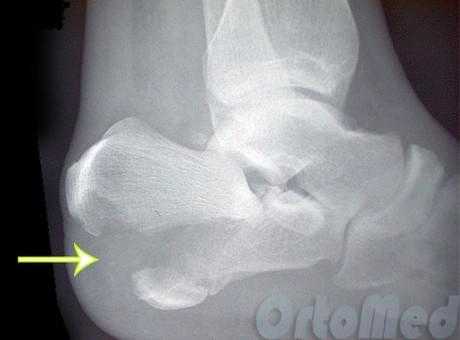

Пациент М. 1980 г.р., травму получил при падении на стопы с высоты 1,5 метра. Лечился по месту жительства (в травмпункте районной больницы) консервативно в гипсовой повязке в течение 14 дней. Консультирован в травматологическом отделении ФГБУ «УНИИТО им. В.Д. Чаклина» Минздрава РФ, предложено оперативное лечение. При поступлении кожные покровы стопы чистые, без признаков воспаления и сдавления тканей. Стопа отечна, уплощена. На рис. 1 представлены рентгенограммы пациента. Прооперирован через 2 недели после травмы. Операция состоит из двух этапов. Первый этап заключается в наложении дистракционного аппарата. Проводятся две спицы 1,8 мм во фронтальной плоскости: первая через нижнюю треть диафиза большеберцовой кости, вторая через бугор пяточной кости (рис. 2). Спицы фиксируются в дистракционном аппарате, выполненном из двух полуколец, соединенных между собой двумя телескопическими тягами. Особое расположение полуколец, фиксация спиц на концах полуколец, крепление кронштейнов для телескопических тяг обеспечивает тракцию пяточной кости в необходимом направлении с использованием минимального количества спиц и внешних опор при сохранении необходимого поля обзора для проведения рентгенологического и визуального контроля репозиции и фиксации. Второй этап - закрытая элевация импрессированной суставной поверхности и окончательная репозиция пяточной кости. Через разрез длиной до 1 см по латеральному краю ахиллова сухожилия (рис. 3) в месте его прикрепления к пяточной кости под соответствующий фрагмент подводится элеватор (рис. 4), манипуляцией которым устраняется смещение и выполняется провизорная фиксация спицами 1,5 мм (рис. 5). При сагиттальном раскалывании суставной фасетки целесообразно проведение одного-двух винтов субхондрально (рис. 6). Стержень вводится с дорзальной поверхности пяточной кости по ее оси через разрез до 2 см по предварительно сформированному остеотомом каналу (рис. 7, 8). Далее через проколы кожи с помощью кондуктора (рис. 9) выполняется запирание винтами с латеральной поверхности, внешнее устройство демонтируется. Достигнуто удовлетворительное стояние отломков (рис. 10).

Рис. 1. На рентгенограмме левой стопы в прямой и боковой проекциях определяется оскольчатый внутрисуставной перелом левой пяточной кости